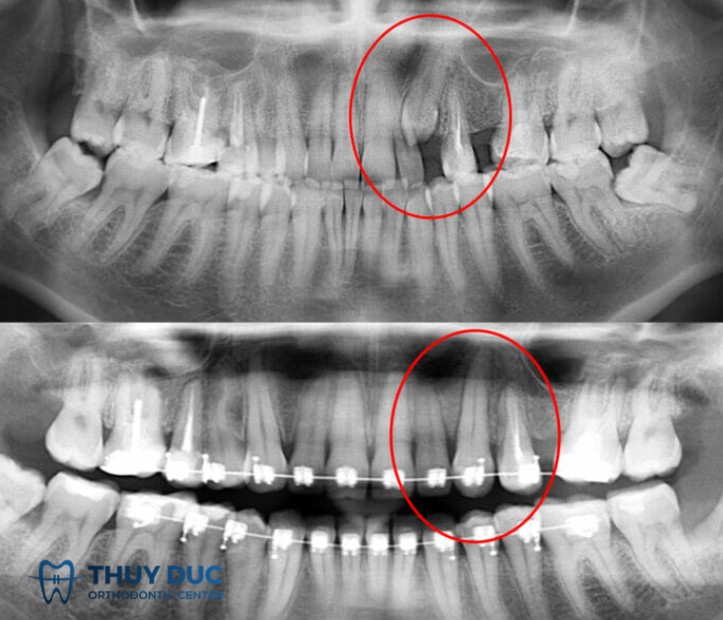

Vì vậy, phương pháp chẩn đoán chính xác nhất là chụp X-quang (thường là phim panorama hoặc phim cận chóp). Trên thực tế, rất nhiều bệnh nhân chỉ phát hiện mình có răng mọc ngầm khi đi khám và chụp phim để điều trị một vấn đề khác, ví dụ sâu răng, viêm nha chu hoặc chuẩn bị niềng răng.

Bác sĩ cần đánh giá toàn diện qua thăm khám lâm sàng, hình ảnh X-quang toàn cảnh hoặc CT Cone Beam để xác định vị trí và hướng mọc. Với răng có giá trị duy trì, đặc biệt là răng nanh hoặc răng cửa, ưu tiên là giữ và đưa răng về vị trí. Ngược lại, với răng khôn hoặc răng không cần thiết, nhổ bỏ thường là lựa chọn tối ưu nếu có nguy cơ biến chứng.